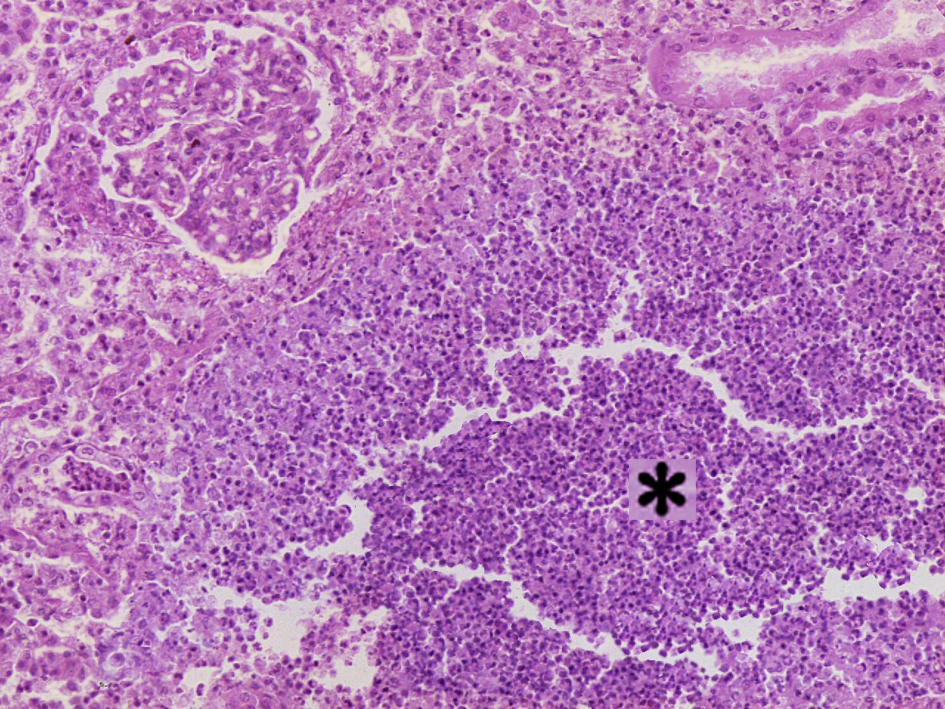

3.急性肾盂肾炎